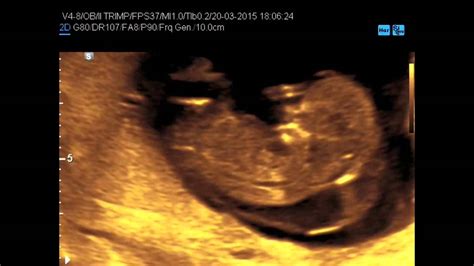

Diagnosi Prenatale e Caratteristiche Ecografiche

L'individuazione dell’igroma cistico avviene di solito nel corso della prima ecografia, tramite l’esame della Translucenza Nucale, tra 9 e 14 settimane di epoca gestazionale, dove si rileva la presenza di una formazione cistica localizzata nella regione postero-laterale del collo fetale. In genere, l'igroma cistico viene diagnosticato intorno alla 12a-14a settimana di epoca gestazionale. Può essere settato o non settato, indicando la presenza o assenza di setti interni all'interno della ciste, che possono influenzare la sua gestione. In presenza di anomalia, vengono poi prescritti altri esami per una valutazione più approfondita. L'ecografia, che può rivelare la presenza di strutture cistiche, è fondamentale per ottenere una diagnosi prenatale accurata.